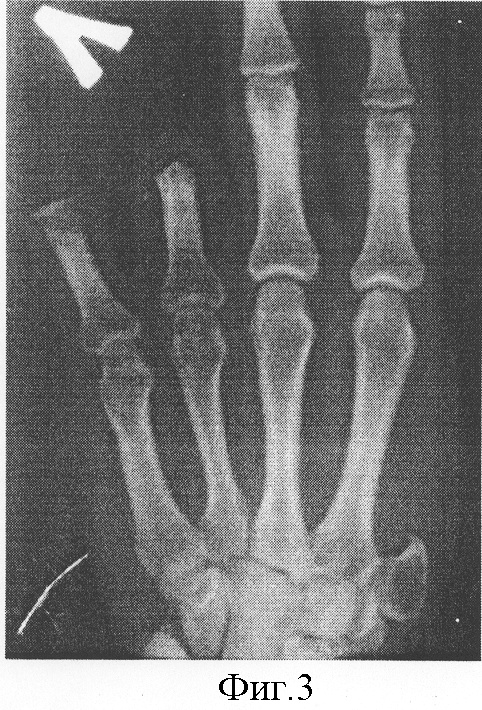

Б-ой С., 1976 г.р. И.Б. №1648, поступил в отделение хирургии кисти НИЦТ “ВТО” 19.04.02. Диагноз: Культя 1 пальца на уровне основания пястной кости, культи основных фаланг 4-5 пальцев левой кисти (Фиг.1, 2, 3,4).